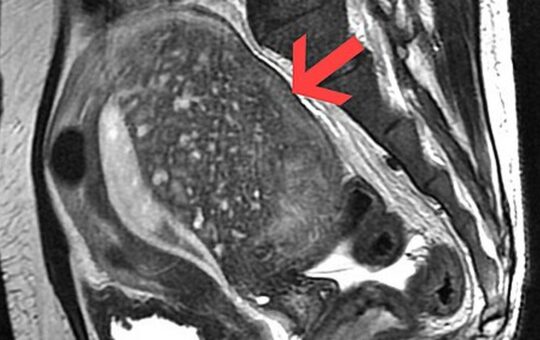

एडेनोमायोसिस के बारे में जानने योग्य सारी बातें

नई दिल्ली, भारतएडेनोमायोसिस एक ऐसी ginecology समस्या है, जो पुरानी पीड़ा और अन्य महिला स्वास्थ्य समस्याओं का कारण बन सकती...